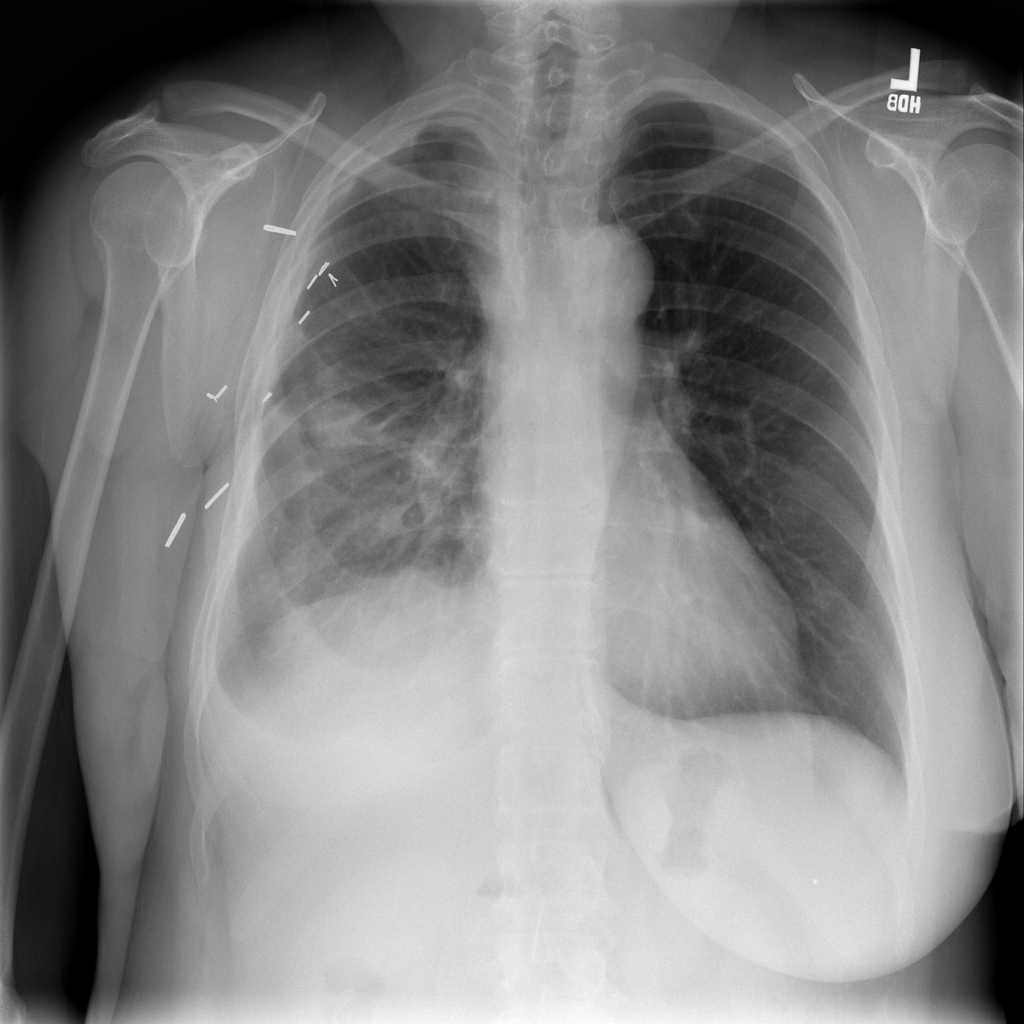

Nodule

A nodule is a small rounded opacity in the lung or chest field. It is a descriptive imaging finding that can be benign or more concerning depending on size, appearance, and context.

Showing up to 90 reference images for Nodule.